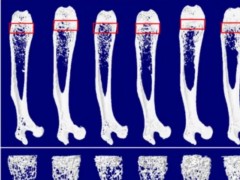

- Nature子刊:陈莉莉团队发现,早晨运动或能最大程度帮助长高